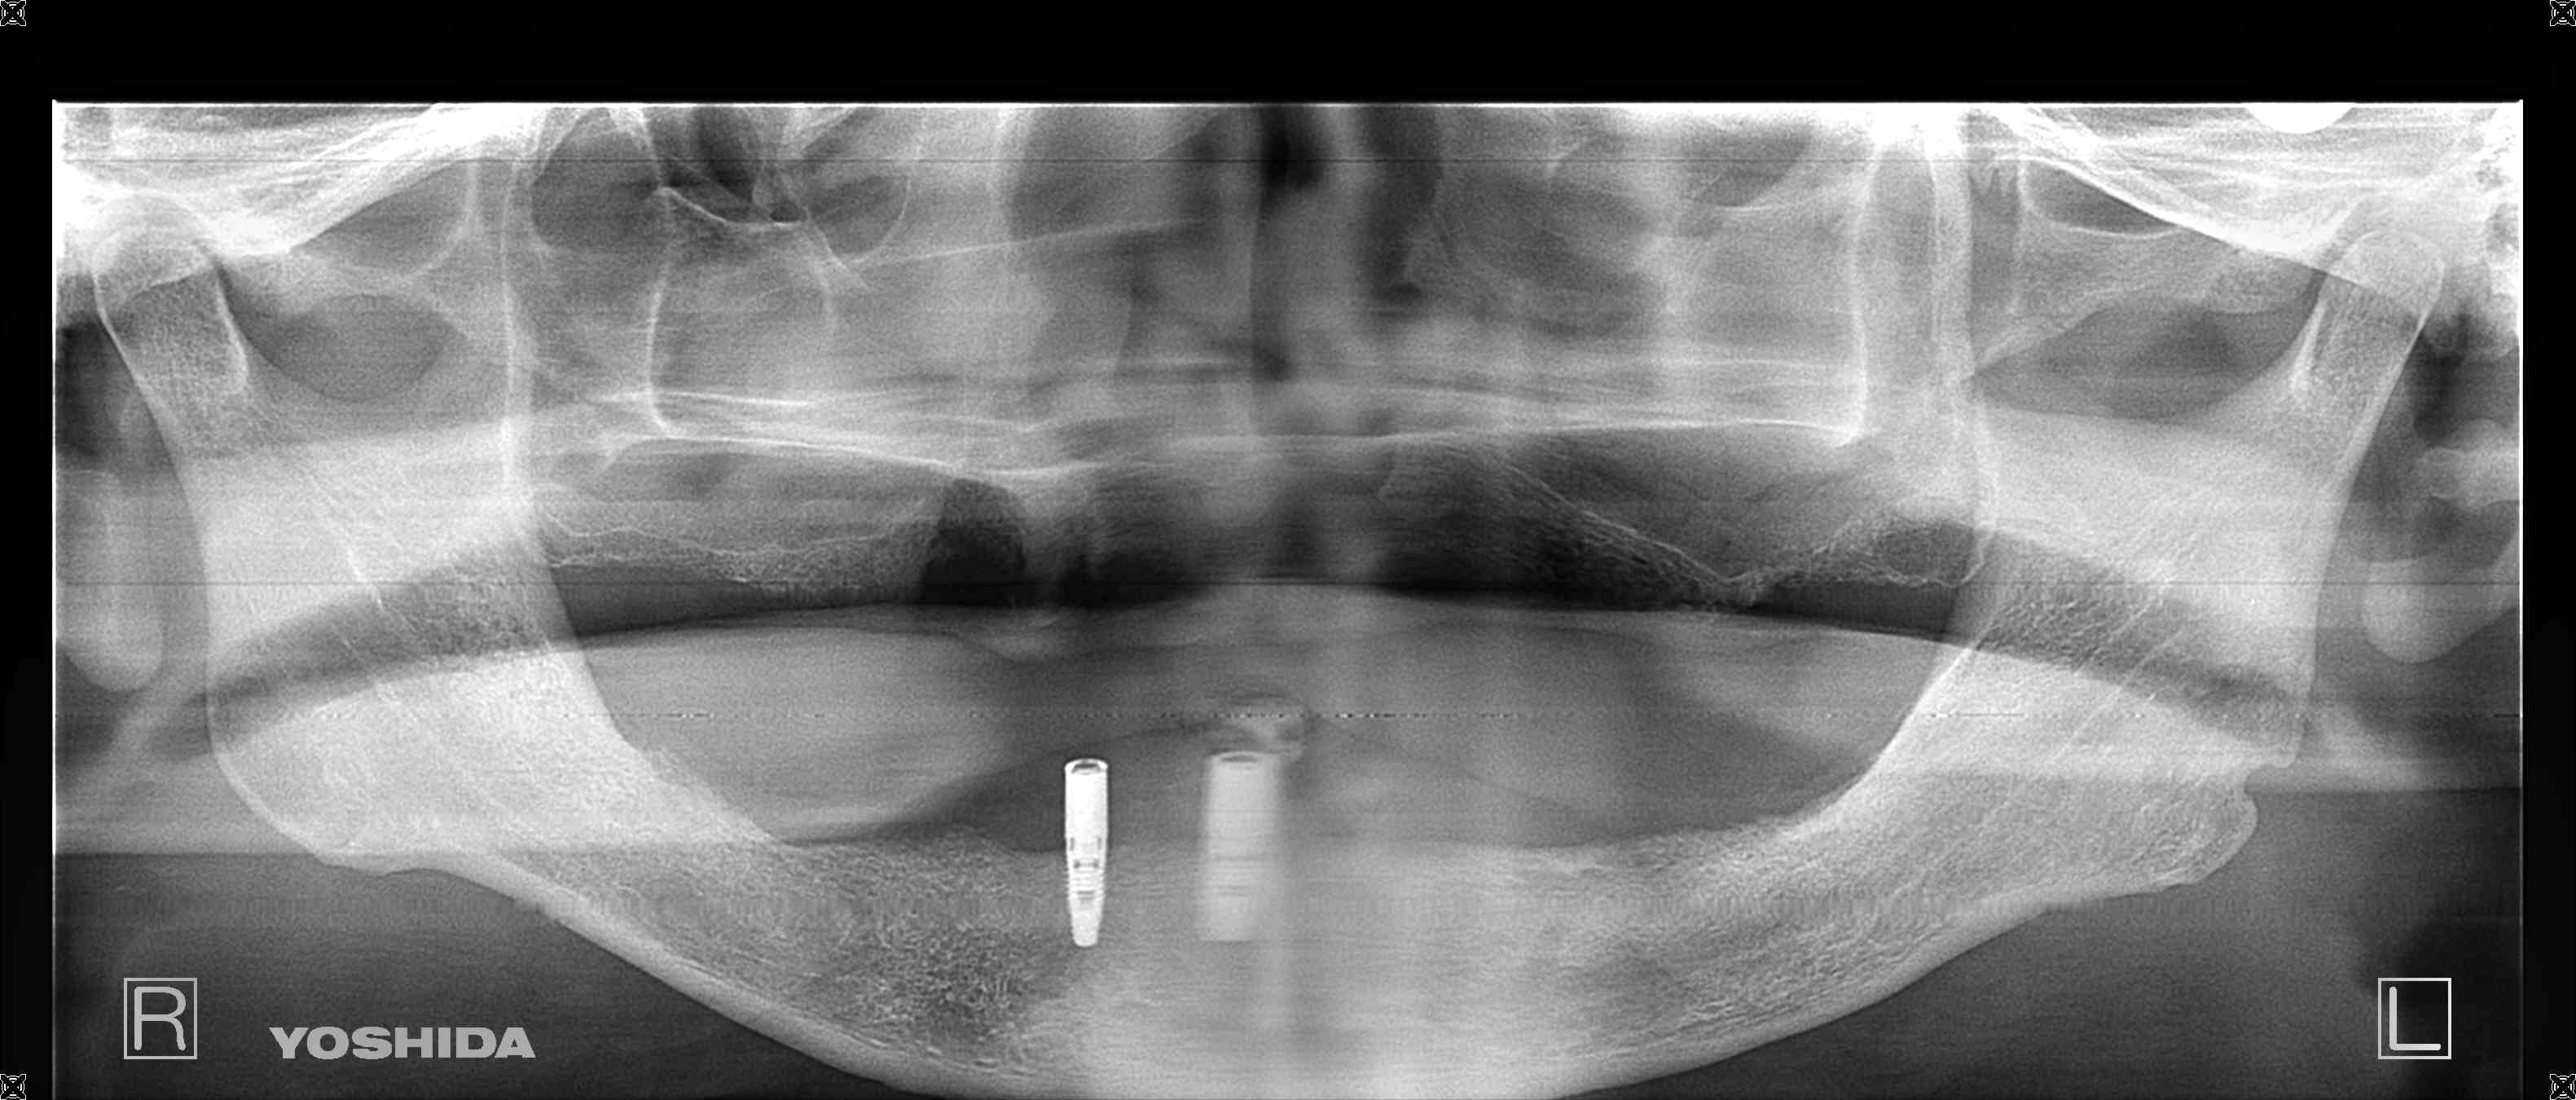

その後、下顎に2本のインプラントを埋入し、3か月後にはインプラントにロケーターアバットメントを装着しました。これは、義歯を安定的に支えるためのパーツで、インプラントに装着された金色のパーツ(赤色矢印)が、入れ歯の安定性を高める役割を果たします。

インプラントを介して咀嚼力が直接下顎の骨(歯槽骨)に伝達されるため、骨の吸収(廃用性萎縮)の予防にも効果があります。